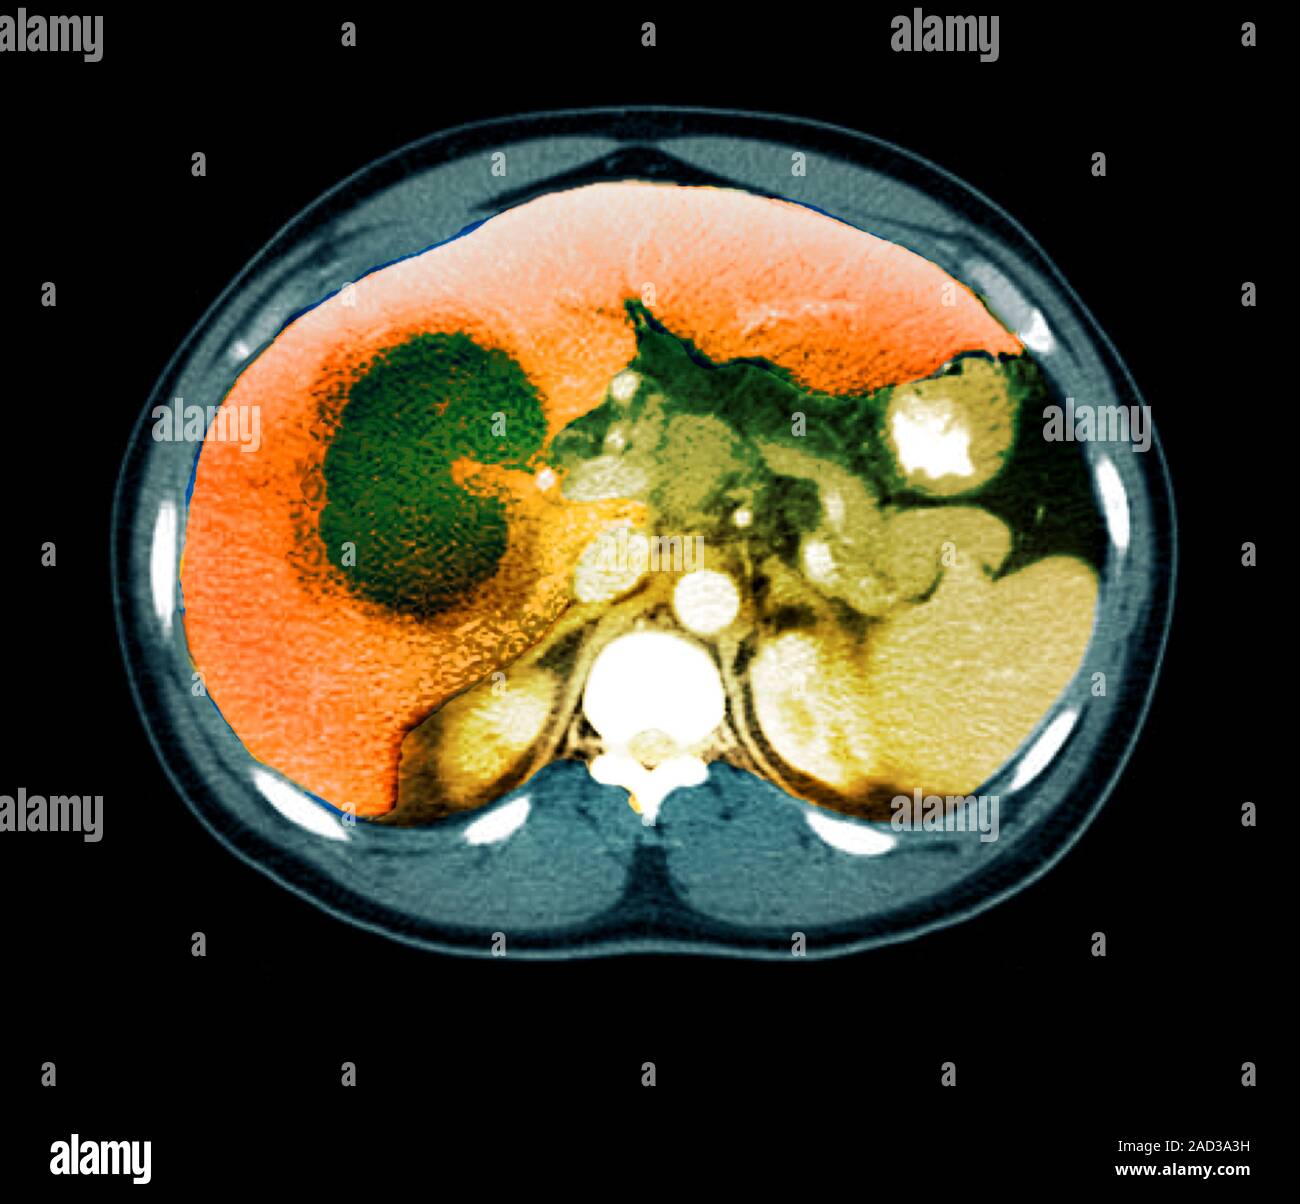

Liver abscess. Coloured computed tomography (CT) scan of an axial section through the abdomen of Liver Abscess X Ray liver abscess is a localized infection in the liver parenchyma that may be bacterial, fungal, or parasitic in origin. Amoebic hepatic abscesses can sometimes be difficult to differentiate from other liver abscesses. imaging tests are the basis of the differential diagnosis of liver abscesses. They tend to be round or. pyogenic liver abscesses usually develops in the. Liver Abscess X Ray.